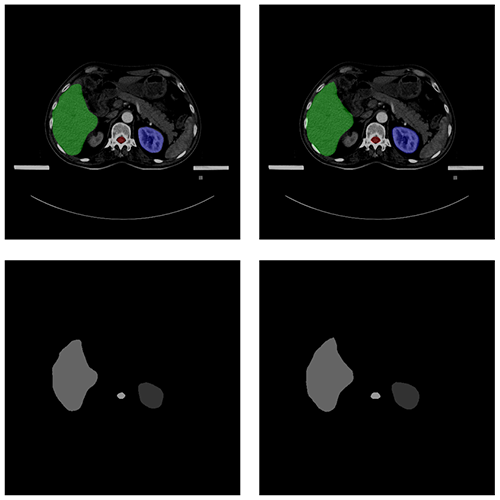

自動(dòng)勾畫效果

AUTOMATIC CONTOURING

原圖

預(yù)測圖